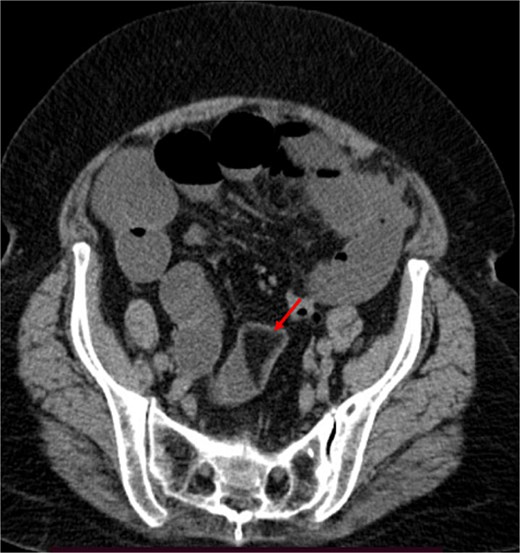

A contrast-enhanced CT of the abdomen was performed and revealed an intraluminal mass in the pylorus causing gastric dilatation (Fig. 1) and another intraluminal mass in the terminal ileum causing small bowel dilatation (Fig. 2). A nasogastric tube was inserted, and the patient was taken for exploratory laparotomy. There were significant gastric and small bowel dilatations; a gastrostomy and enterostomy were performed, and two foreign bodies were extracted (Fig. 3). The incision sites were then repaired.

The arrow indicates an intraluminal mass in the small bowel causing proximal small intestinal obstruction.